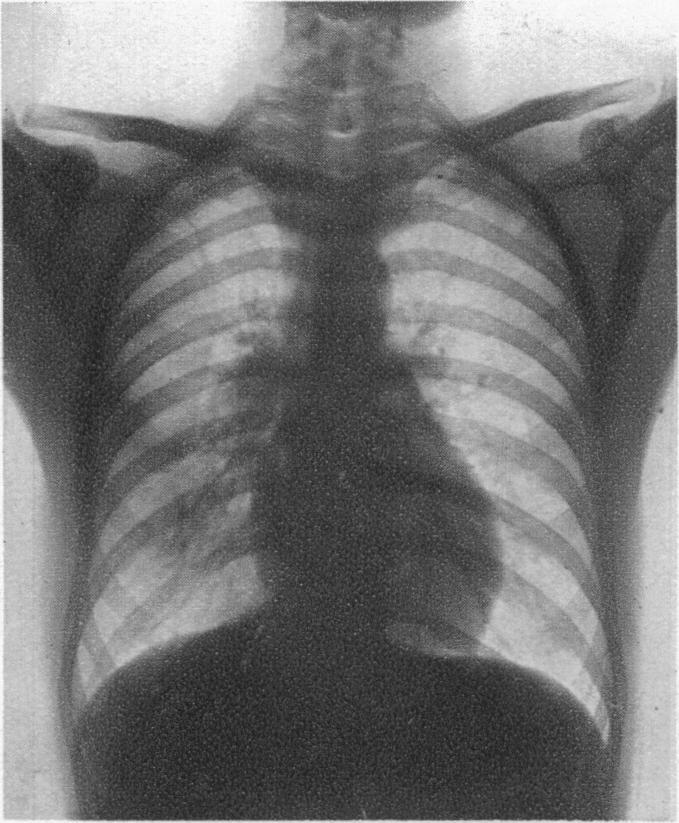

Pneumonitis.